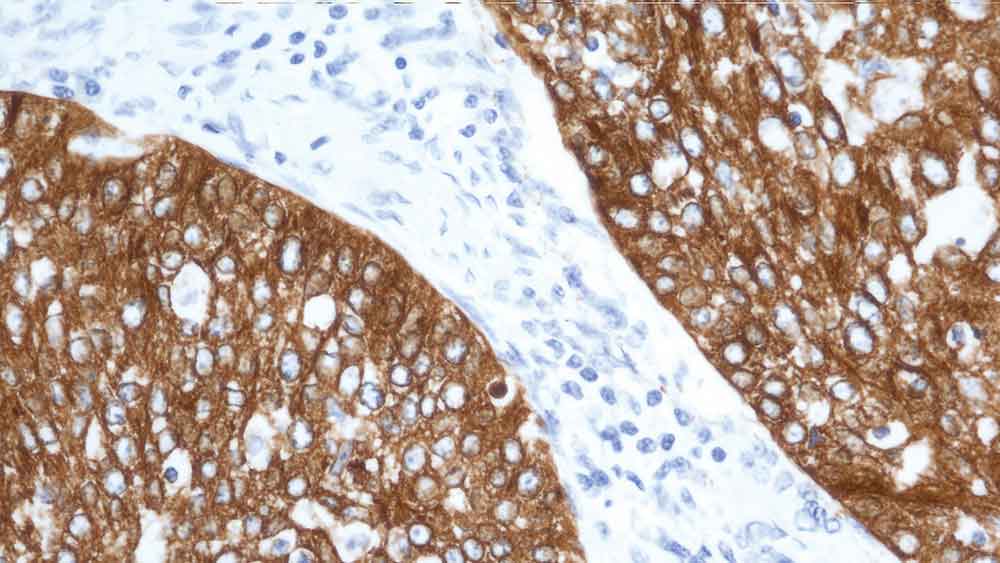

Human tonsil: immunohistochemical staining for CD19. Note membrane staining of B cells. CD19: clone BT51E

CD19 is a member of the immunoglobulin superfamily and has two Ig like domains. It is a single chain glycoprotein present on the surface of B lymphocytes and follicular dendritic cells of the hematopoietic system. CD19 is a crucial regulator in B cell development, activation, and differentiation. On B cells, CD19 associates with CD21, CD81, and CD225 (Leu-13) forming a signal transduction complex. CD19 is expressed from the earliest recognizable B cell lineage stage, through development to B cell differentiation but is lost on maturation to plasma cells.